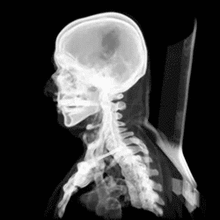

من مكتشف أشعة X | مكتشف أشعة X | أشعة X: تُعتبَر أشعة إكس (بالإنجليزيّة: X-rays) شكلاً من أشكال الإشعاع الكهرومغناطيسيّ الذي تتعدَّد أشكاله، مثل: موجات الردايو، والأشعّة تحت الحمراء، والأشعّة فوق البنفسجيّة، وأشعّة الميكرويف، حيث إنّ مصدرها هو تسارُع الإلكترونات، ويتمّ استخدام هذا النوع من الأشعّة في المجالات الطبّية، والأكثر شيوعاً هو استخدامها في التصوير الطبّي، بالإضافة إلى استخداماتها في علاج السرطان، وينتقل هذا الإشعاع على شكل موجات بتردُّدات وأطوال موجيّة مختلفة يُطلَق عليها اسم الطَّيف الكهرومغناطيسيّ. وينقسم الطَّيف إلى سبع مناطق حسب تناقُص طول الموجة، و زيادة الطاقة، والتردُّد، وهناك نوعان من الأشعّة السينيّة، وهما: الأشعّة السينيّة الليِّنة، والأشعّة السينيّة الصلبة، وتتميَّز الأشعّة السينيّة الليِّنة بأنّها تحتوي على تردُّدات عالية، كما أنّ أطوال موجاتها قصيرة، وهي تحتلُّ المنطقة بين الأشعّة فوق البنفسجيّة، وأشعّة جاما على الطَّيف الكهرومغناطيسيّ، وتقع في منطقة أشعّة جاما نفسها على الطَّيف الكهرومغناطيسيّ، وتُستخدَم أشعّة إكس في عدّة مجالات في الطبّ، مثل: إجراء أشعّة لسرطان العَظم، وأورام الثدي، وتضخُّم القلب، والكسور، والمشاكل التي تحصل في الجهاز الهضميّ، وتسوُّس الأسنان والتهاب المفاصل.

بسبب مقدرة أشعّة إكس على اختراق موادّ مُعيَّنة، يتمّ استخدامها في عمليّات التفتيش الأمنيّ، وعند نَقْل البضائع والركّاب؛ حيث تسمحُ هذه الأشعّة، ومن خلال أجهزة الكَشْف عن الصور الإلكترونيّة، بتصوير محتويات الحقائب، والأمتعة، كما أنّها تُستخدَم في تصوير العِظام، وهي تُستخدَم كطريقة غير مُؤلِمة؛ لتشخيص المرض، ومراقبة العلاج، إضافة إلى أنّها تساعد في دَعْم العاملين في المجال الطبّي عند إدخالهم دعامات، أو أيّة أجهزة داخل الجسم، كما أنّ لها دوراً في علاج الأورام، وإزالة الانسدادات، والجلطات الدمويّة؛ وذلك لأنّ أشعّة إكس المُؤينة تُرسِّب كمّيات كبيرة من الطاقة في منطقة صغيرة؛ إذ تُجرِّد هذه الطاقة الإلكترونات من الذرّات، وهذا يؤدّي إلى تغيُّر في خصائصها الكيميائيّة، وكَسْرٍ للروابط الجزيئيّة، وبالتالي تَلَف الخلايا، أمّا إذا تمّ توجيهها إلى الخلايا السرطانيّة، فإنّها سوف تقتلها. ويلجأ الطبيب إلى استخدام الأشعّة السينيّة؛ للمراقبة، ولتشخيص مرض مُعيَّن، أو مراقبة تطوُّر مرض تمّ تشخيصه، أو للتحقُّق من مدى فعاليّة ونجاح علاج ما، ولالتقاط صورة باستخدام أشعّة إكس، يتمّ ارتداء ملابس فضفاضة؛ لتحريكها بسهولة، بالإضافة إلى أنّه لا بُدّ من نَزْع أيّة مجوهرات، أو أيّ عناصر معدنيّة، وقد تستدعي الحاجة تناوُل مادّة مُتبايِنة، وظيفتها المساعدة في تحسين نوعيّة الصورة، حيث قد تحتوي هذه المادّة على مُركَّبات اليود، أو الباريوم.